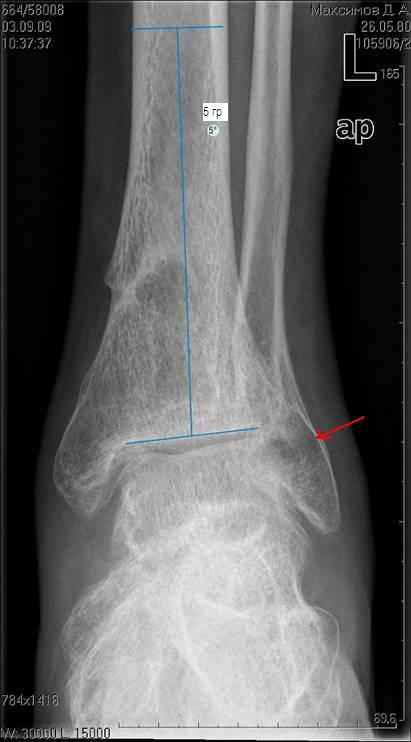

Здравствуйте коллеги. Представляю молодого человека 28 лет, получившего травму в апреле

2008года.

Травму он получил на работе, левая голень со стопой оказались зажатыми между двумя тяжелыми

предметами. В результате открытые переломы 1,2,3 плюсневых костей с размозжением мягких

тканей над ними, открытый перелом наружней лодыжки со смещением дистального отломка кзади и

подвывихом стопы кнаруже с размозжением мягких тканей над лодыжкой, закрытые переломы

внутренней лодыжки и дистального метэпифиза большеберцовой кости. Учитывая наличие

размозжения тканей стопы и области голеностопного сустава лечили в аппарате внешней

фиксации. Перелома срослись, однако имеет место незначительный подвывих стопы кнаруже и

неправильно сросшийся отломок наржной лодыжки (смещен кзади) Сегодня пациента ничего не

беспокоит (с его слов. Клинически левый голеностопный сустав не отечный,пальпация всех

структур данного сустава безболезненна. Имеет место ограничение тыльного сгибания стопы

(сгибание к тылу стопы составляет до 10-15 гр), в связи с этим имеет место гиперподвижность в

суставе Шопара. Пациент ходит со стельками (индивидуальные). Нужна ли пациенту

реконструктивная операция в голеностопном суставе:исправление в взаимоотношений в

наружних отделах голеностопного сустава или что еще?